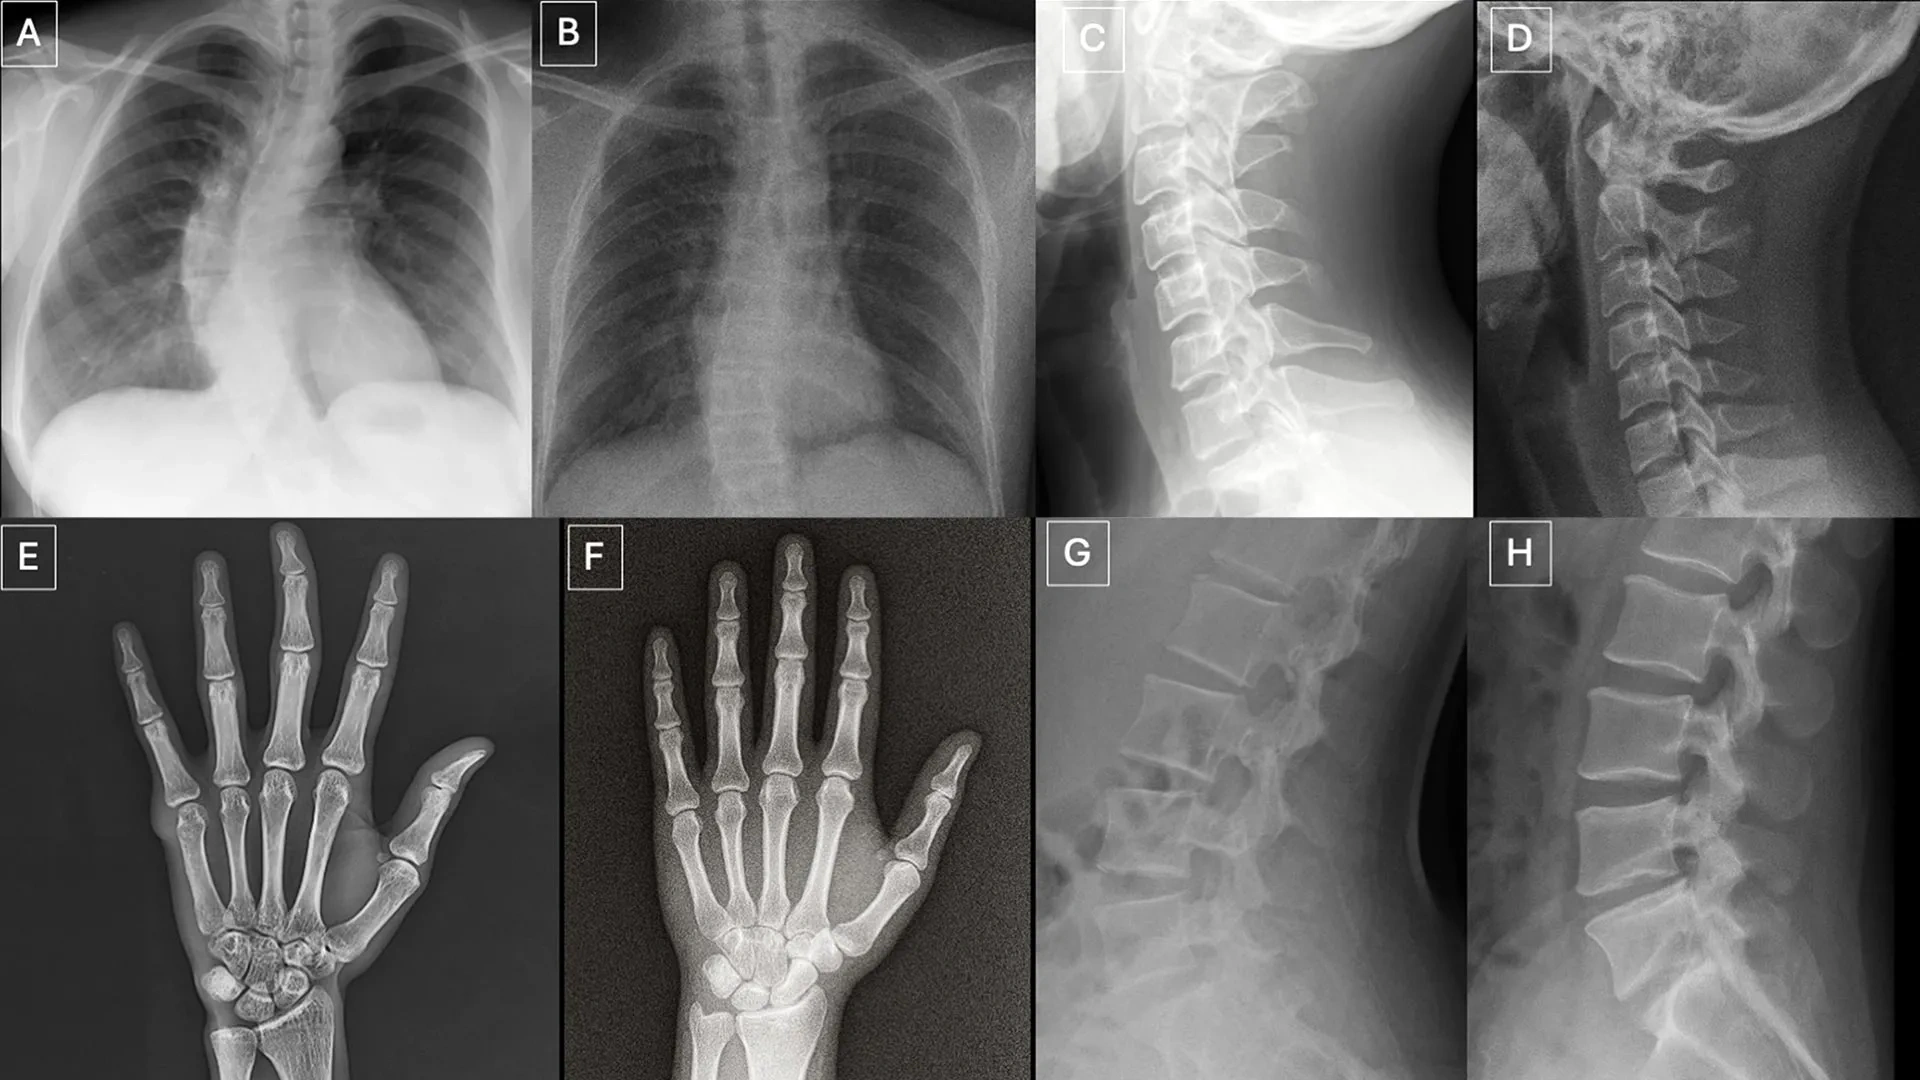

图源:The association between parent-child relationship and orthodontic compliance with clear aligners among children and adolescents